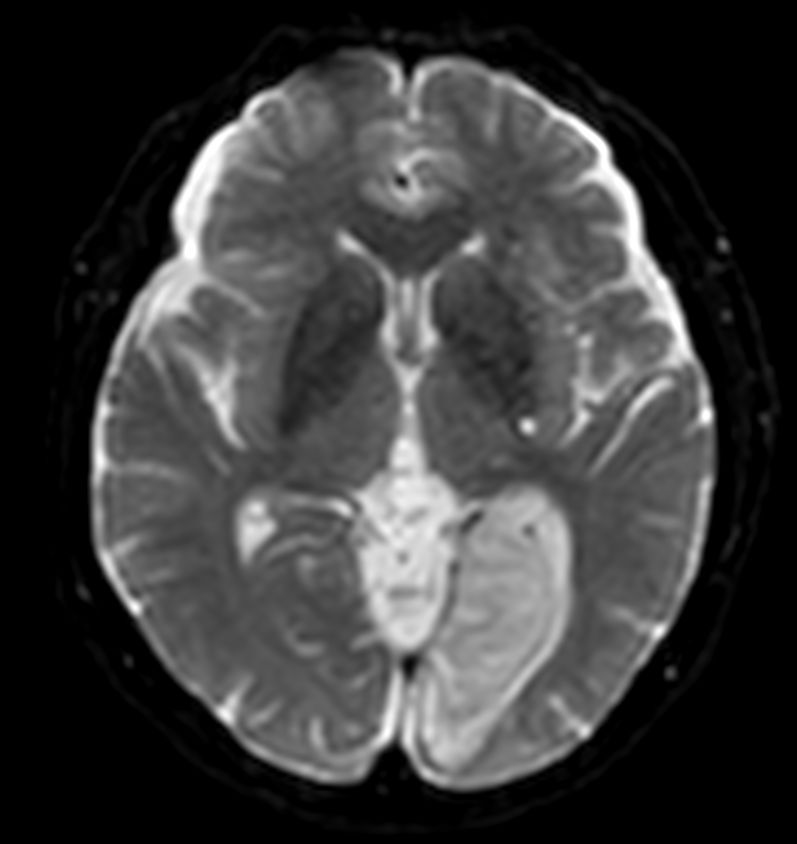

Diffusion - b0

-

Diffusion - b1000